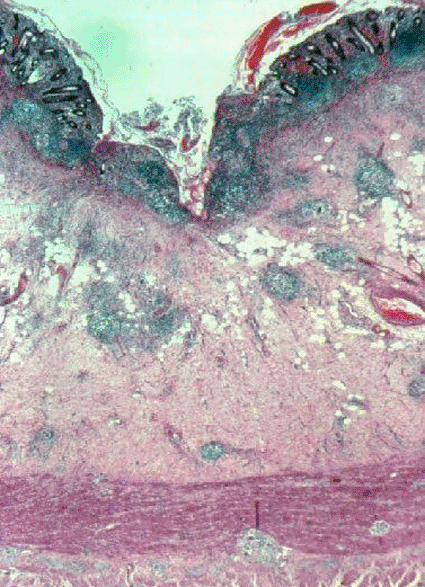

Image: Light micrograph of the human small intestine in Crohn’s disease (Photo courtesy of Biophoto Associates).

A team of scientists tested DNA samples from patients with Crohn's disease, comparing them with normal DNA samples. The investigators conducted a genome-wide association scan of approximately 20,000 ‘coding' genetic variants that are thought to produce functional changes at the protein level. A novel genetic variant in a gene was identified and verified that had not been previously associated with Crohn's disease. The protein-coding genetic variation identified provides evidence that an abnormal immune response to bacteria in the digestive tract may lead to the intestinal inflammation characteristic of Crohn's disease.